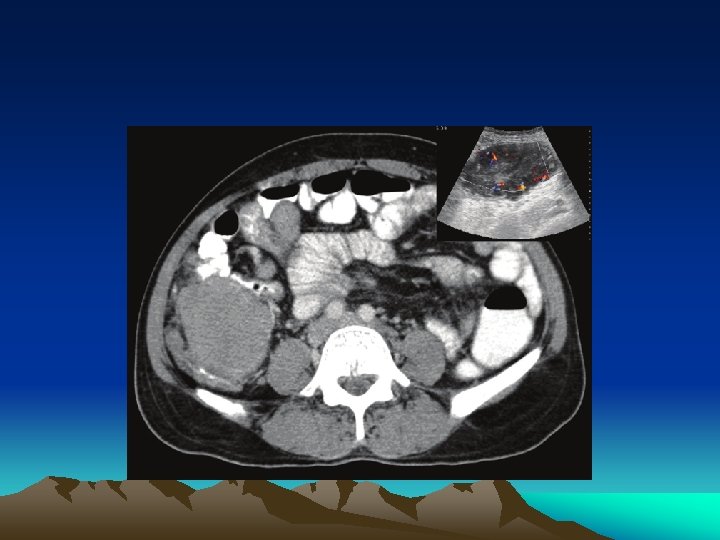

Surgery for Metastatic Disease metastases to: -lung -brain -liver can be controlled by surgical resection -

Metastasectomy This is done when: • The primary tumor is controlled or can be controlled • Metastasis is single or multiple • Evidence that metastasectomy is associated clinical benefits • Tumor doubling time is sufficiently long • No significant co-morbid factor

Metastasectomy • Complete resection of distant metastases improves five-year overall survival rates • 40% for colorectal cancer with resection of liver metastases • 30% for sarcoma with resection of lung metastases • 16% for breast cancer with resection of brain metastases